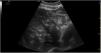

We report the case of a 53-year-old woman admitted to the intensive care unit (ICU) due to bilateral intraparenchymal hemorrhage requiring mechanical ventilation. Following the insertion of a nasogastric tube, the hepatic ultrasound reveals the presence of multiple heterogeneous hyperechoic images (Fig. 1). Microbubbles were also identified, on M-mode, in the portal vein and its visible branches (Fig. 2). A follow-up ultrasound performed 8h later confirmed the disappearance of all these findings (Fig. 3).

These events are indicative of aerobilia due to the infusion of air for epigastric region auscultation of the correct placement of the nasogastric tube, which is probably in the duodenum with an incompetent papilla.